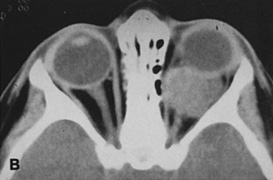

Figure 10. A. Large, well-encapsulated intraconal mass on MR scan. B. Small lateral canthotomy incision will be used to perform lateral orbitotomy and remove the intraconal mass.